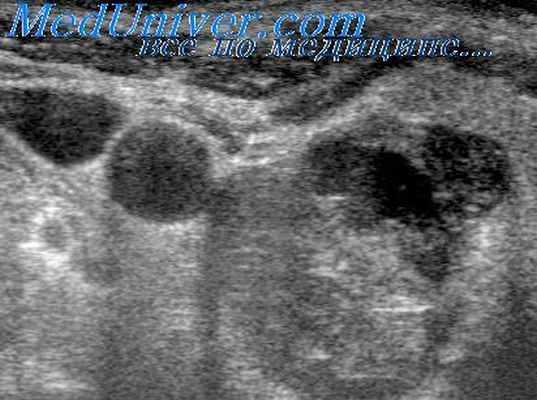

Фолликулярная аденома представляет собой доброкачественную опухоль щитовидной железы, имеющую железистое или фолликулярное строение. Эта опухоль обычно одиночная и менее 3 см в диаметре. Она имеет тенденцию к медленному росту внутри капсулы из окружающей, сдавленной железистой ткани щитовидной железы. С течением времени развивается плотная капсула, окружающая образование. Сонографически аденома обычно является солидным образованием, которое может быть изо-, гипо- или гиперэхогенным. Вокруг нее может определяться периферический гипоэхогенный ободок вследствие наличия фиброзной капсулы. Капсула может быть гладкая и толстая, а кистозная дегенерация представлена единичными или множественными фокусами.

Геморрагические кисты чаще всего образуются в результате спонтанных кровотечений внутри фолликулярной аденомы. Сонографически, геморрагические кисты проявляются как прозрачные для звука образования с неровными контурами и множественными внутренними перегородками.

- УЗИ. Данное исследование позволяет увидеть округлой формы узел, с ободком вокруг него, что говорит о наличии хорошо выраженной капсулы опухоли.